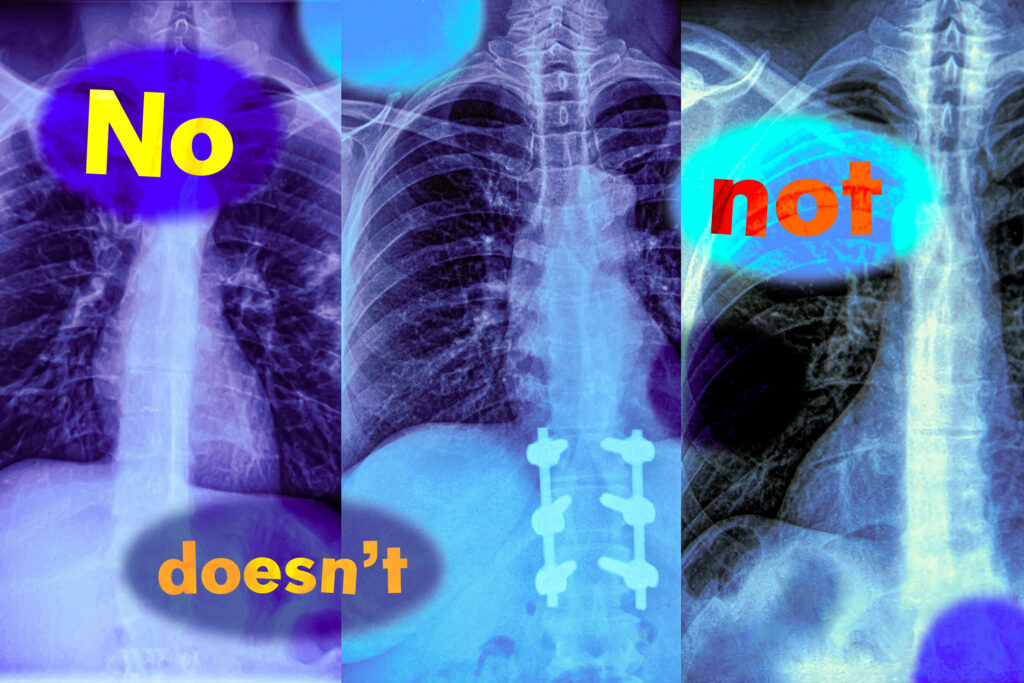

Imagine a radiologist examining a chest X-ray from a new patient. She notices the patient has swelling in the tissue but does not have an enlarged heart. Looking to speed up diagnosis, she might use a vision-language machine-learning model to search for reports from similar patients.

But if the model mistakenly identifies reports with both conditions, the most likely diagnosis could be quite different: If a patient has tissue swelling and an enlarged heart, the condition is very likely to be cardiac related, but with no enlarged heart there could be several underlying causes.

In a new study, MIT researchers have found that vision-language models are extremely likely to make such a mistake in real-world situations because they don’t understand negation — words like “no” and “doesn’t” that specify what is false or absent.